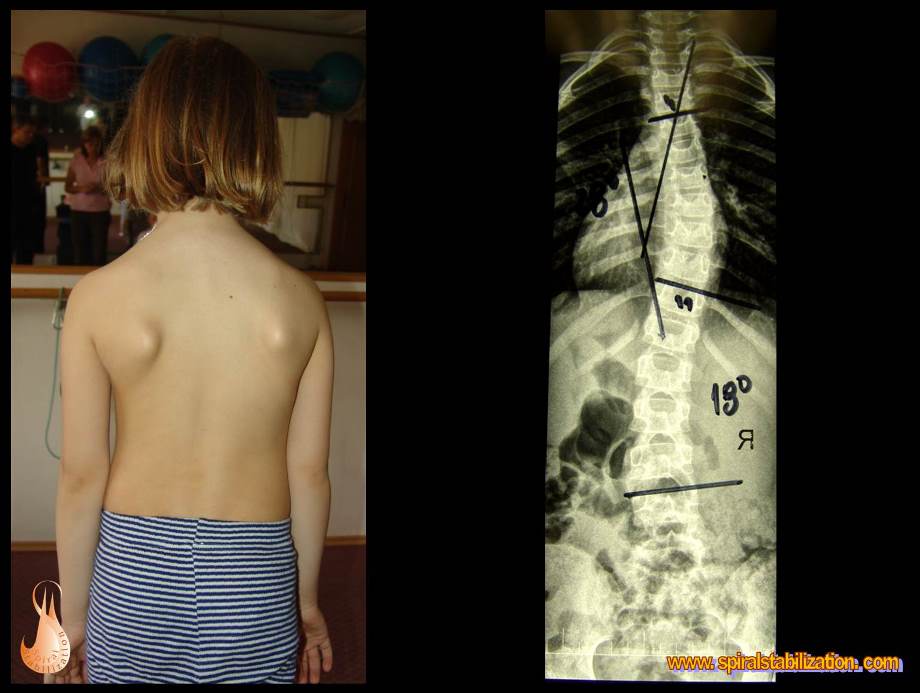

Skoliózu môžeme charakterizovať ako trojrozmernú deformitu so sklonom a posunom stavcov vo frontálnej (stranové zakrivenie), sagitálnej (zmeny fyziologickej lordózy a kyfózy) a tranzverzálnej (rotácia chrbticového stĺpca) rovine. Jednoducho povedané, je to chorobné vykrivenie chrbtice mimo jej prirodzenú krivku.

U idiopatickej (z neznamej príčiny) skoliózy spočiatku nie sú štrukturálne zmeny stavcov. U skoliózy sú najviac dislokované telá stavcov, ich oblúky a výbežky menej. Obvykle viditeľný je typický hrb pri rotácii chrbtice v hrudnej časti, kde priečne výbežky sú nasledované rebrami a vytvára sa tak tzv. paravertebrálna prominencia (prominencia = výčnelok). Najviac viditeľná je deformita pri Adamsovom teste - v predklone.

Veľkosť deformity sa hodnotí vo všetkých troch rovinách. Metódou podľa Cobba možno odčítať uhlovej zakrivenie v predozadnej projekcii (AP = Antero-posterior) a v bočnej projekcii (sagitálnej rovine). Modernými zobrazovacími metódami možno navyše v osovom reze trupu (v transversálnej rovine) odčítať rotáciu chrbtice.